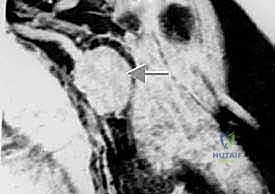

- التصوير بالرنين المغناطيسي (MRI) بالصبغة: الفحص الأهم على الإطلاق. يحدد بدقة متناهية حجم الورم، امتداده داخل النخاع العظمي، وعلاقته بالأعصاب والأوعية الدموية.

3. التسليك الوعائي والعصبي (Neurovascular Dissection)

هذه هي المرحلة الأكثر خطورة. باستخدام أدوات الجراحة الميكروسكوبية وعدسات التكبير، يقوم الدكتور هطيف بفصل الشريان والوريد الإبطي، والضفيرة العضدية عن كتلة الورم. يتطلب هذا دقة متناهية، فأي خطأ قد يؤدي إلى نزيف حاد أو شلل دائم في اليد.